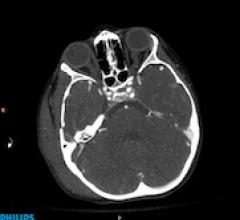

Computed tomography angiography (CTA) is one of the most complex procedures routinely performed on a CT scanner. A ...

While CT angiography (CTA) is a complex procedure, Philips Ingenuity CT has advanced features to simplify CTA planning ...